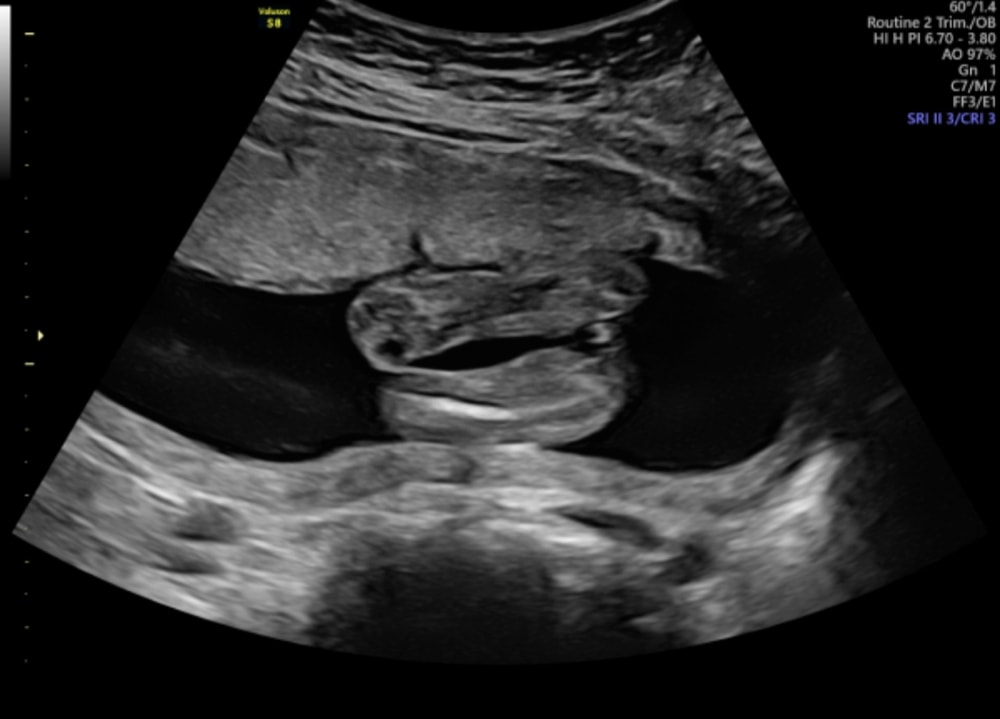

Вчера писала пост про то, что меня уверяли на УЗИ, что это мальчик, нашла ещё вот этот снимок с того же УЗИ, я конечно сдам кровь на определение пола, но вопрос всё тот же, где тут можно увидеть яички 😀😀 По-моему девочка-девочка прям

Ну, так, конечно, больше на девочку похоже)

Но, если врач прям так уверен - то сложно быть уверенной в обратном)

Анастасия, ну у вас и срок поменьше) я не знаю просто как тут можно увидеть не девочку 😀